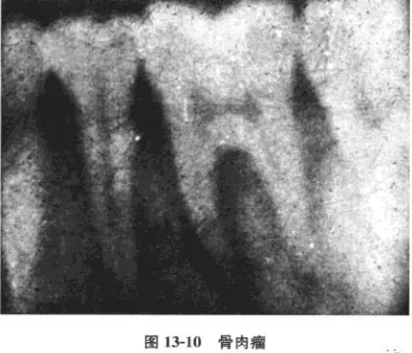

病例 男性,18歲,[6極度松動(dòng),咀嚼痛伴局部腫大而就診。檢查:[6III度松動(dòng),牙髓活力測試無反應(yīng),牙周袋3~5mm,左下頜角打及3mm×3mm之腫塊,邊界尚清,質(zhì)地中等偏軟,無壓痛,x線片示:[6兩根側(cè)及根分叉對稱性牙周間隙增寬。為確診腫塊性質(zhì),轉(zhuǎn)口腔頜面外科,攝下頜骨正側(cè)位片,見左下頜角有溶骨性破壞,手術(shù)后病理診斷為骨肉瘤。

口腔頜面部肉瘤可分為軟組織肉瘤和骨源性肉瘤兩大類;骨肉瘤根據(jù)不同的病理表現(xiàn)又有骨纖維肉瘤、成骨性骨肉瘤、溶骨性骨肉瘤以及軟骨肉瘤等不同類型。骨肉瘤起源于頜骨中心或牙槽內(nèi)者可早期表現(xiàn)為牙松動(dòng)、牙齦腫脹等類似牙周炎的表現(xiàn)。x線攝片可見牙周間隙呈帶狀(或呈平行)增寬,而且常常是近遠(yuǎn)中同時(shí)發(fā)生。本病例因牙痛就診,牙髓活力無反應(yīng),伴牙松動(dòng)及牙周袋存在,若非在其后側(cè)觸及腫塊,極易誤診為牙周病及根尖周病,或牙髓牙周聯(lián)合病變。其x線片亦表現(xiàn)為較典型的早期骨肉瘤破壞陰影(圖13-10),為此,作為牙體牙髓科醫(yī)師必須具有此基本概念和知識(shí);更重要的是決不能忽視口腔頜面部的全面檢查,以保證診斷的正確性。